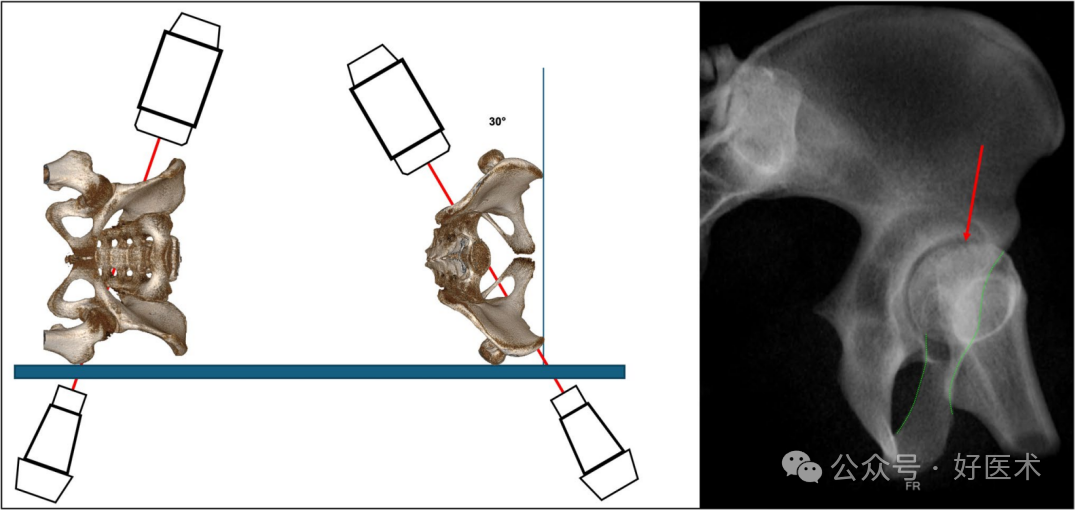

髋臼上螺钉通道是骨盆环固定中常用的通道。典型的螺钉应用指征包括髋臼上外固定中的顺行针置入、腰骶固定中的逆行螺钉置入、S2髂嵴(S2AI)螺钉应用,这是经典后路固定技术的改良,从骶骨后部S1和S2神经孔之间开始,穿过骶髂关节,沿着髋臼上缘骨通道,特别适用于骨质疏松性骨和骨盆环新月形骨折的固定,可显著提高固定强度。最近,根据Young-Burgess骨折分类,插入该通道的螺钉被描述为LC-II螺钉,该分类包括一个LC-II亚型,用于稳定完全性后髂骨骨折和新月形骨折。另一种适应症是根据Rommens分类的IIIA型脆弱性骨折,或者具有高位前柱骨折的髋臼骨折,也可以使用这种技术进行固定。该骨通道从髂前下棘(AIIS)开始,沿着骨盆边缘平行且略向外侧延伸,在到达骶骨后上棘(PSIS)或髂前上棘(PIIS)之前,位于大坐骨切迹上方(图17)。

图 17 使用真侧位视图、COOO、骨盆入口和 CIOO 视图(从左到右)对髋臼上通道 (SAC) 进行放射成像观察。

对于SAC,建议所有可能的标准视图及其组合,包括标准PAP、OOV、IOV、COOO、PIV、TLV、COOI和CIOO。最相关的视图是髂骨外侧外斜位(COOO),在这个视图中,通道呈现出泪滴形状。泪滴形状的下部应**位置于直接与髋臼顶(sourcil)相切的位置,且泪滴形状应尽可能小,以便**地确定螺钉的入口点。在插入螺钉时,应考虑关节囊附着点可延伸至髋臼顶(sourcil)上方16毫米处。经典的髂骨外侧斜位(IOV)确认螺钉放置在大坐骨切迹上方的**位置。为了术中分析螺钉路径,建议采用多种视图(图17):

TLV(髂骨斜位):确认螺钉位于大坐骨切迹上方。

COOO(髂骨外侧外斜位):分析从骶骨后上棘(PSIS)到髂前下棘(AIIS)的骨通道内螺钉的轴向方向(起始点);可以排除螺钉的内侧或外侧穿透。

PIV(髂骨内侧斜位):确认螺钉路径位于骶髂关节的外侧。

IOV(髂骨外侧斜位):确认螺钉路径位于大坐骨切迹上方,并分析螺钉长度。

COOI(髂骨外侧内斜位):分析髂骨的外侧和内侧边界。

建议采用的视图有 COOO、COOI 和 IOV 以及将植入物插入 SAC 的 TLV。